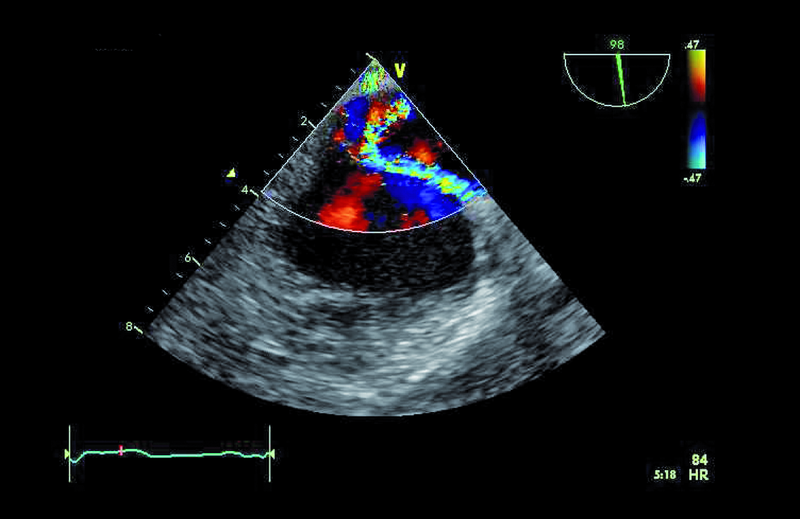

Podstawowym celem terapii jest opanowanie procesu zapalnego. Zazwyczaj kilkutygodniowe (4-6 tygodni) podawanie antybiotyku pozwala osiągnąć taki cel. Należy jednak spytać o wskazania do leczenia operacyjnego. Niezwykle ważna w ocenie jest wielkość wegetacji. Zgodnie ze standardami wskazaniem do operacji jest wegetacja większa niż 15 mm lub wegetacja >10 mm, która stanowiła źródło zatorowości. Żadne z dwóch kryteriów nie było u chorej spełnione. Nie było także epizodu duszności, obrzęku płuc ani innych objawów niewydolności serca. Niedomykalność mitralną oceniono na umiarkowaną. Charakterystyczne dla niej były dwa strumienie fali zwrotnej – jeden centralny wynikający z perforacji płatka tylnego oraz drugi równoległy do płaszczyzny pierścienia zastawki, wynikający z wypadania płatka (ryc. 5). Jama lewej komory była niepowiększona, a kurczliwość mięśnia prawidłowa (ryc. 6). Zdecydowano o postępowaniu zachowawczym z kilkutygodniową skojarzoną antybiotykoterapią. W toku obserwacji zaplanowano kolejne badanie przezprzełykowe z oceną ewentualnej zmiany wielkości wegetacji.